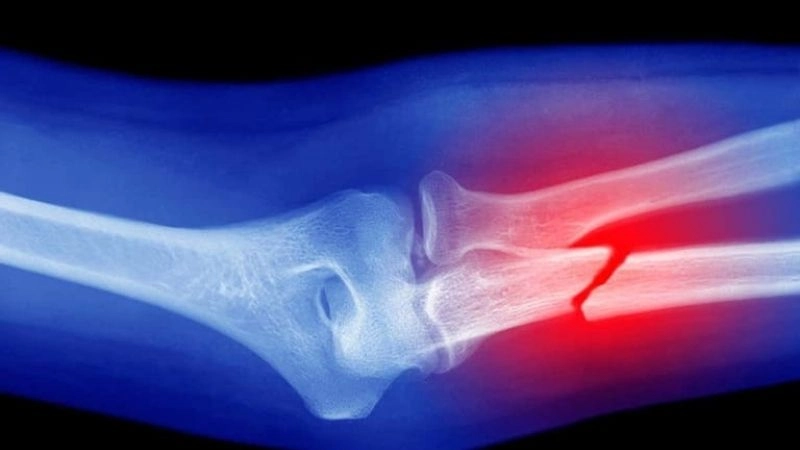

Gãy xương là gì?

Gãy xương là tình trạng xương bị biến dạng, gãy đôi theo chiều dọc hoặc chiều ngang hoặc gãy thành nhiều phần. Một người có thể gặp chấn thương này ở bất kỳ khu vực nào trên cơ thể nếu chịu tác động lực quá mức. Ngoài ra, để thúc đẩy quá trình hồi phục diễn ra nhanh chóng, người bệnh nên được thăm khám bác sĩ ngay khi bị chấn thương hoặc phát hiện các dấu hiệu xương bị gãy.

Gãy xương là tình trạng xương bị biến dạng